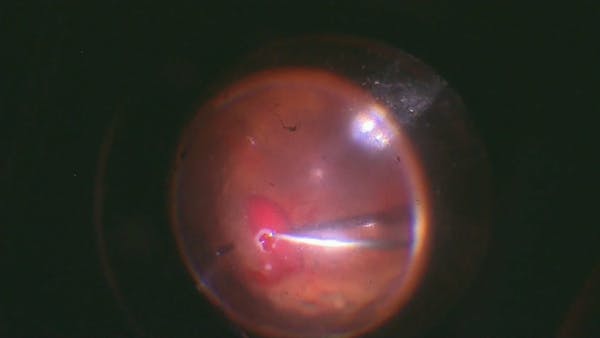

TRD 25g Lift & Peel Technique

Maria H. Berrocal, MD

Surgery for Macular Hole and Retinal Detachment

Roberto Alejandro Guerra Garcia, MD